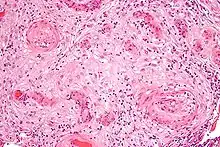

Role in pre-eclampsia

Pre-eclampsia is a disorder found in around 5% of pregnant women, usually presenting in the 37th week of gestation, with prognosis ranging from mild to severe.[7] While mild forms of the disease do not significantly impact mother or fetus, more severe cases may lead to blood vessel constriction, increased blood pressure, and reduced blood flow. This in turn can damage various organ systems including the brain, liver, kidneys, and heart. Dangers to the fetus occur when restricted blood flow due to high pressures causes a lack of blood flow to the uterus. This can result in a number of problems for the fetus including poor growth, lack of amniotic fluid, and placental abruption.[7]

The cause of pre-eclampsia is not known. Research indicates that the tachykinin peptide neurokinin B may play a role, as placental expression of the TAC3 gene, which codes for NKB, was found in high levels in women with pre-eclampsia.[8]

Usually not located in peripheral tissue, high levels of TAC3 gene were found in both maternal plasma and placental blood, including blood from the umbilical cord. TAC3 in this case was able to secrete NKB in order to affect the circulation of the fetus. Additional studies done on rodents introduced to high levels of NKB indicated the vasoregulatory properties of the peptide, such as the vasoconstriction found in cases of pre-eclampsia.[8]

Increased NKB secretions seem to be caused by defective implantation or invasion of the embryo at the trophoblast stage. In most cases of pre-eclampsia, the trophoblast was unable to fully invade into the uterine lining and has been an almost constant feature in documented cases. This leads to increased signaling of NKB factors. In cases of defective implantation, NKB is vital to increase blood flow to the placenta. However, it seems as though depending on which receptor NKB binds, the peptide can cause both constriction and dilation of the blood vessels. The NK1 receptor was studied and found to cause vasodilation while the NK3 receptor was found to cause vasoconstriction. Higher levels of NK3 receptor seem to be found in pregnant woman suffering from pre-eclampsia. NKB usually found in the brain, has been found in the placenta at a concentration of 2.6 times that of the NKB in the brain,[8] possibly leading to the onset of pre-eclampsia in mothers.